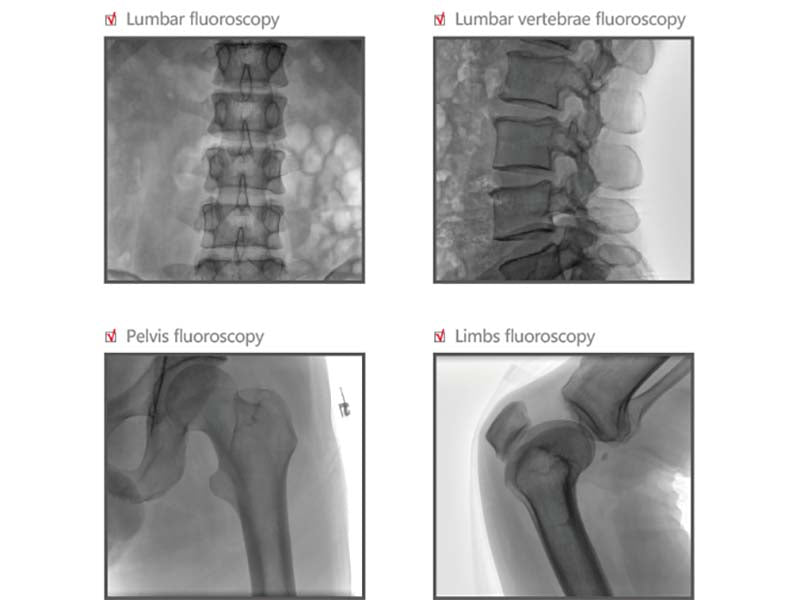

- RCDP – rapid calculate display platform GPU-based dynamic real-time image processing technology makes it easy to get sharp image of various body parts.